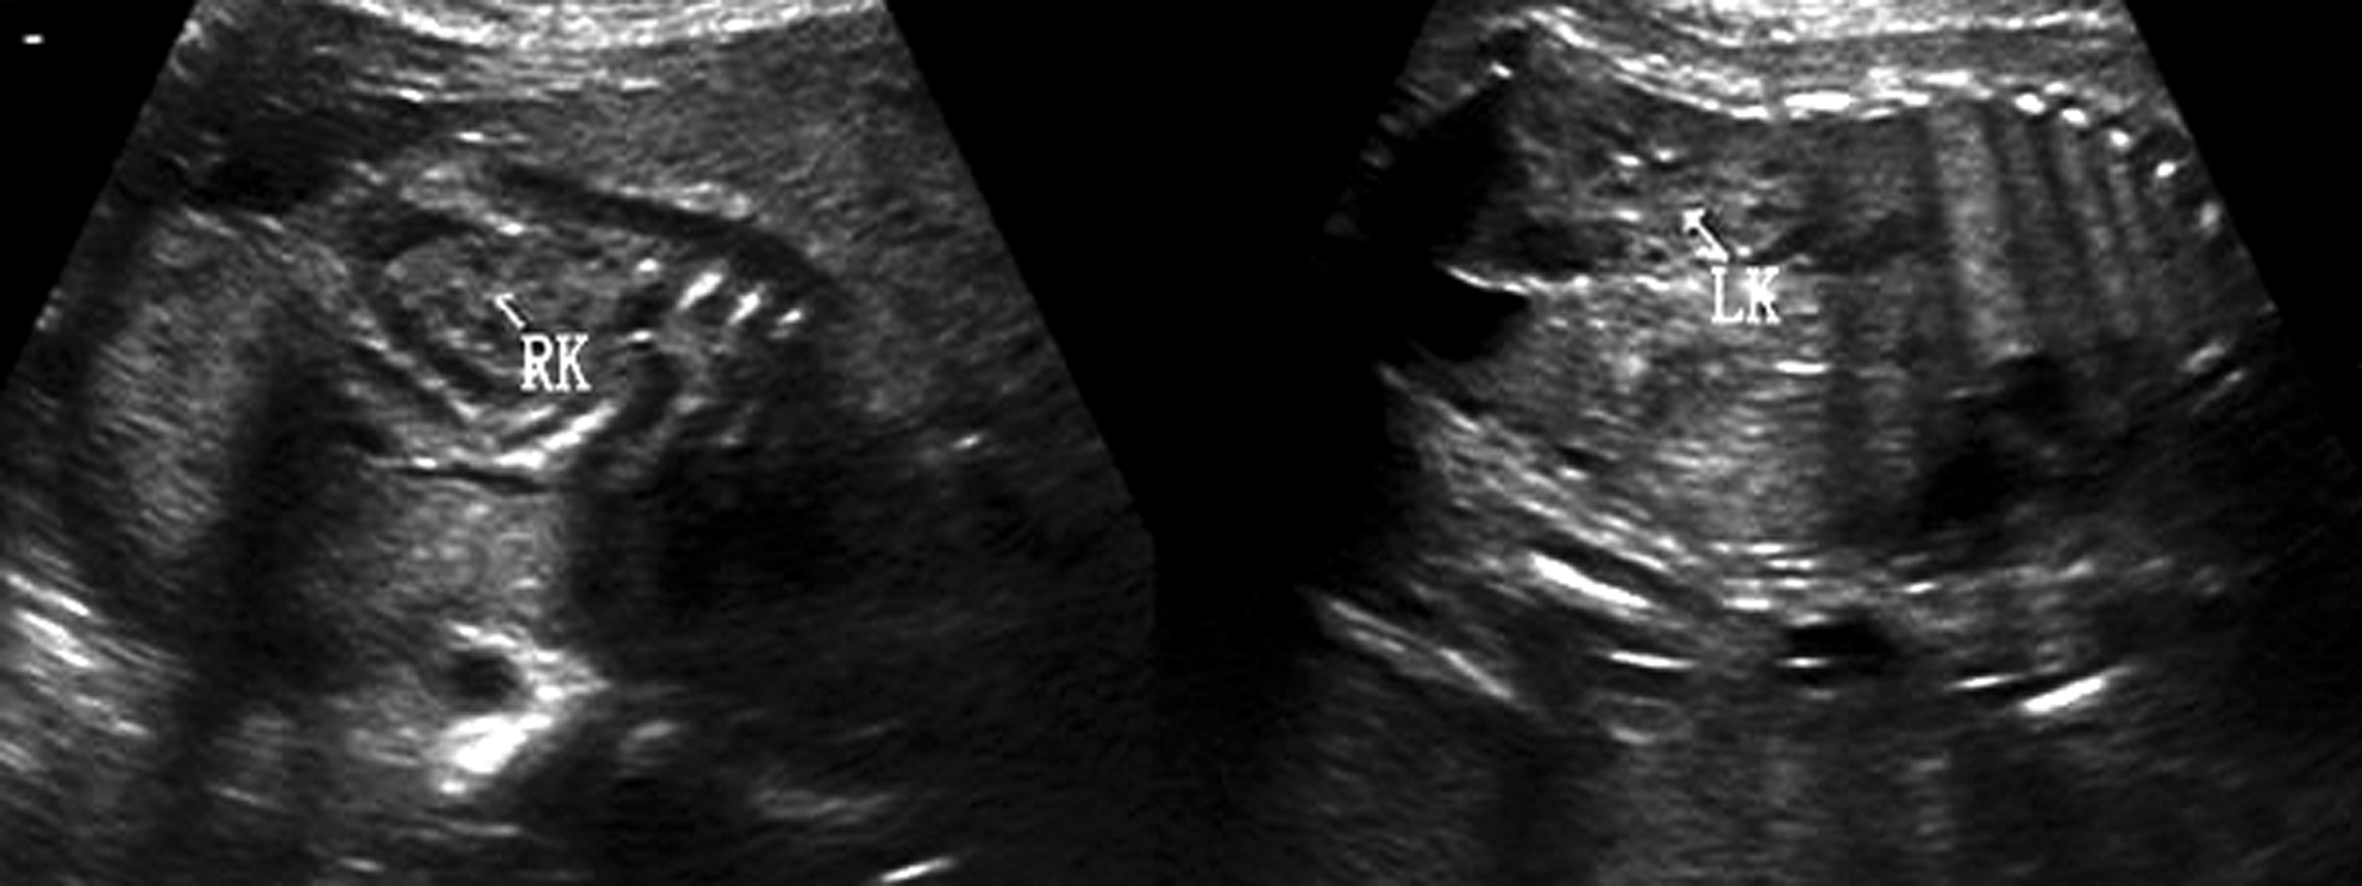

1.肾脏 孕14周时可显示出胎儿双肾,18周后可清晰显示(图5)。正常肾脏位于脊柱两旁,低于成人肾的位置,在腹部脊柱旁矢状面上呈长圆形蚕豆样,肾脏水平横切时呈圆形,右侧(RK)稍低于左侧(LK)。最初胎儿肾脏为均匀的低回声区结构。随着妊娠的进展,可见到更为详细的内部结构。等回声的肾皮质包绕在低回声的锥形髓质周围,中央强回声区为集合系统,肾盂呈无回声长条状结构,位于集合系统中央。肾外周为肾周脂肪和肾囊。当超声显像检查肾脏回声显示不清时,CDFI检查肾动脉有助于确认肾脏的存在(图6)。肾脏周长、容积、厚度和长度均与孕龄有良好的相关性,正常肾脏长度相当于4~5个椎体的高度;在整个妊娠期肾周长/腹围保持在比较恒定的0.27~0.30之间。

图5胎儿双肾纵切面声像图